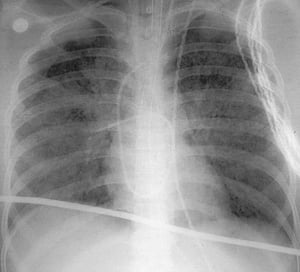

Sindrome da distress respiratorio acuto

Questa radiografia del torace in posizione verticale mostra opacità bilaterali diffuse caratteristiche della sindrome da distress respiratorio acuto.

Questa radiografia del torace in posizione verticale mostra opacità bilaterali diffuse caratteristiche della sindrome d

By permission of the publisher. Da Herdegen J, Bone R. In Atlas of Infectious Diseases: Pleuropulmonary and Bronchial Infections. Edited by G Mandell (series editor) and MS Simberkoff. Philadelphia, Current Medicine, 1996.